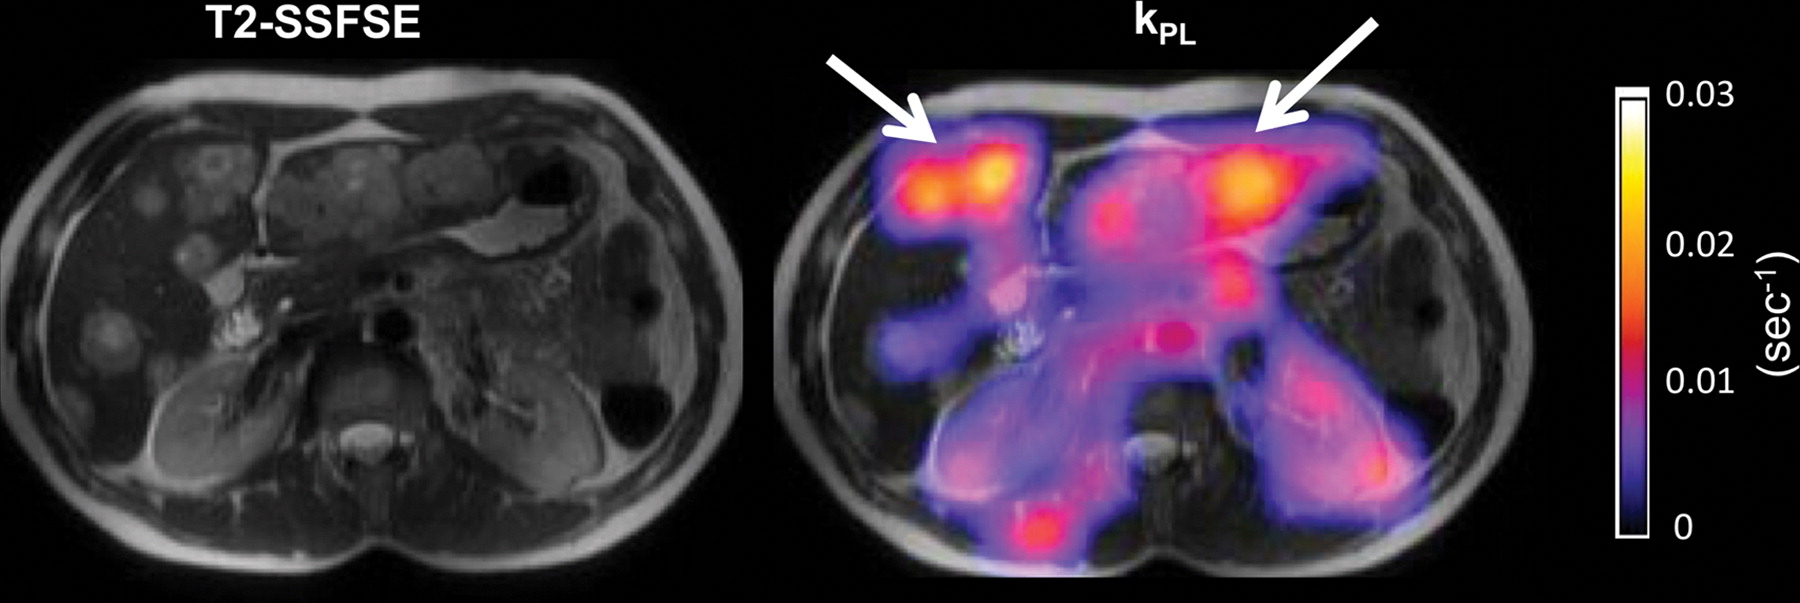

图7: 乳腺癌转移至肝脏的患者的超极化(HP)[1-13C]丙酮酸MR图像。

该研究使用16通道腹部碳13(13C)线圈阵列进行,允许覆盖整个上腹部和动态13C回波平面光谱成像技术,时间分辨率为2秒。

T2加权单次快速自旋回波(SSFSE)图像(左)显示多发性肝转移。

在T2加权SSFSE图像上叠加的kPL(每秒丙酮酸盐 - 乳酸盐转化的表观速率常数)图(右)显示具有升高的丙酮酸盐 - 乳酸盐转化的肝转移(箭头),与代谢活性一致肿瘤。